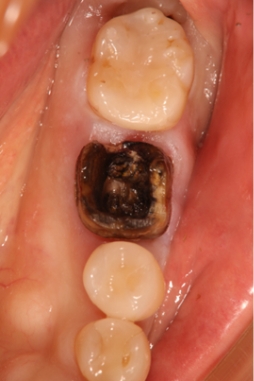

銀歯の下の歯は唾液の侵入によって黒変し、虫歯も生じ歯根破折を起こしている。

特に銀歯は金銀パラジウム合金が口の中で溶けてアレルゲンとして全身に作用し、種々のトラブルを引き起こすことが明らかにされています。